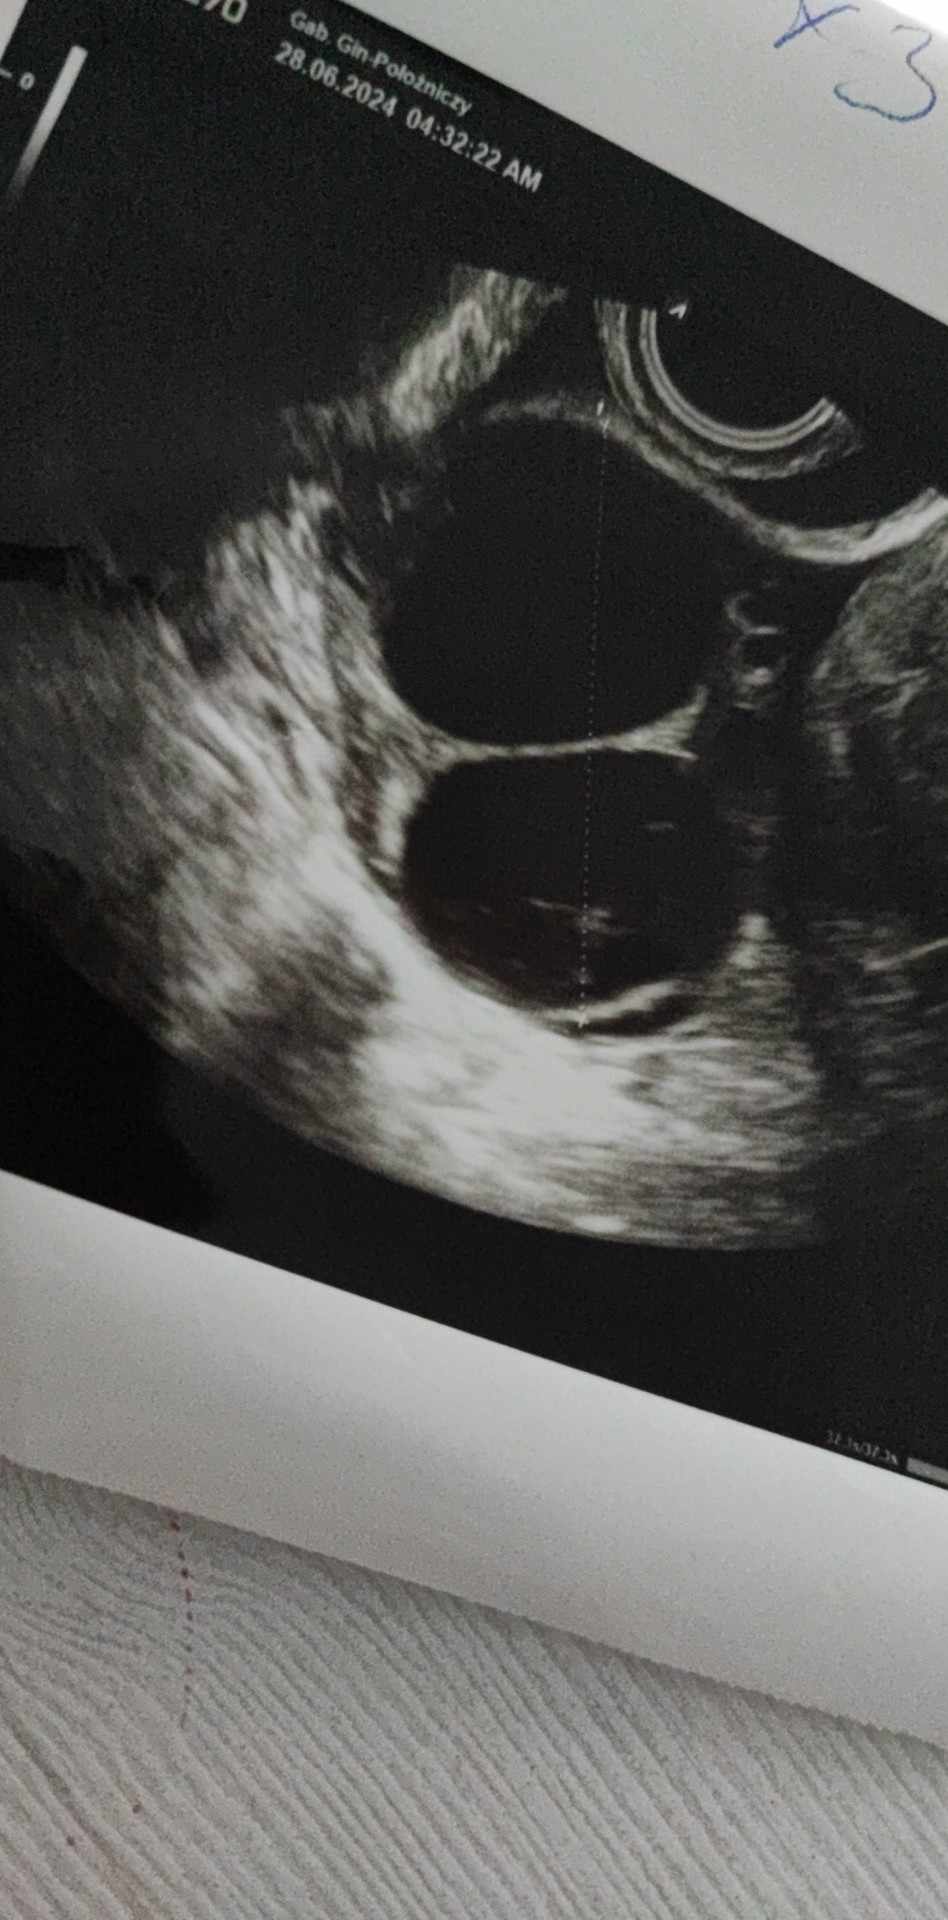

Torbiel na jajniku a ciąża

Cześć, spóźnia mi się miesiączka 8 dni, dziś 43 dzień cyklu, cykle mam co 34-35 dni, w piątek byłam u ginekologa ponieważ dwa testy pokazały lekką drugą kreseczkę a dwa były z jedna kreska. Lekarz stwierdził torbiel na prawym jajniku wielkości 5cm ale sam do końca nie wiedział czy może jednak jestem w ciąży czy nie zasugerował tylko że jeśli jest wczesna to jej nie widzi. Powiedział że miesiączka powinna wystąpić do tygodnia ale nie czuje żeby się na nią zapowiadało co zrobić w sytuacji gdy miesiączka nie pojawi się? Iść jeszcze raz do niego? Dodam też że kazał zacząć brać tabletki antykoncepcyjne gdy rozpocznie się miesiączka. Jak oceniacie te usg?

Rozumiem, a po USG pani coś wnioskuje? Bo jak dla mnie to dziwne te dwa pęcherzyki czy jak to nazwać inaczej a w tym jednym jakby cień nwm czy to jakiś płyn

Wygląda na torbiel z resztą tak jak mówił lekarz.